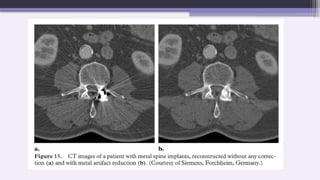

MAR (Metal artifact reduction) technique:-

Acquisition and storage of the raw data

Reconstruction of CT image

Identification of the implant

Automatic definition of the boundaries of the implant within the

projection data. For each projection, the implant boundaries are

automatically defined within the given ROI by the use of given

threshold values

Iterative reconstruction of the missing projection data

Reconstruction of the artifact-reduced image from the newly

computed projection data